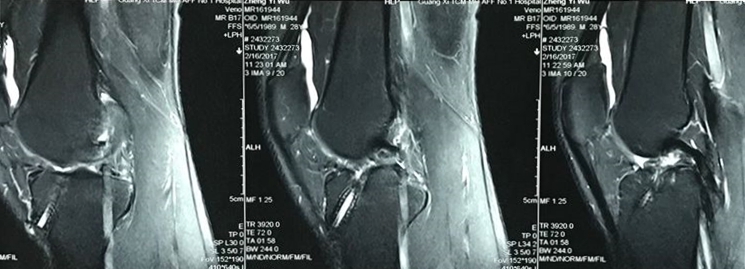

患者男性,外院行左膝ACL重建术后3年,膝关节一直松动,不能运动。MRl检查显示重建的ACL消失,股骨及胫骨隧道位置不佳。

CT检查显示ACL重建的胫骨隧道偏前,股骨隧道偏后。